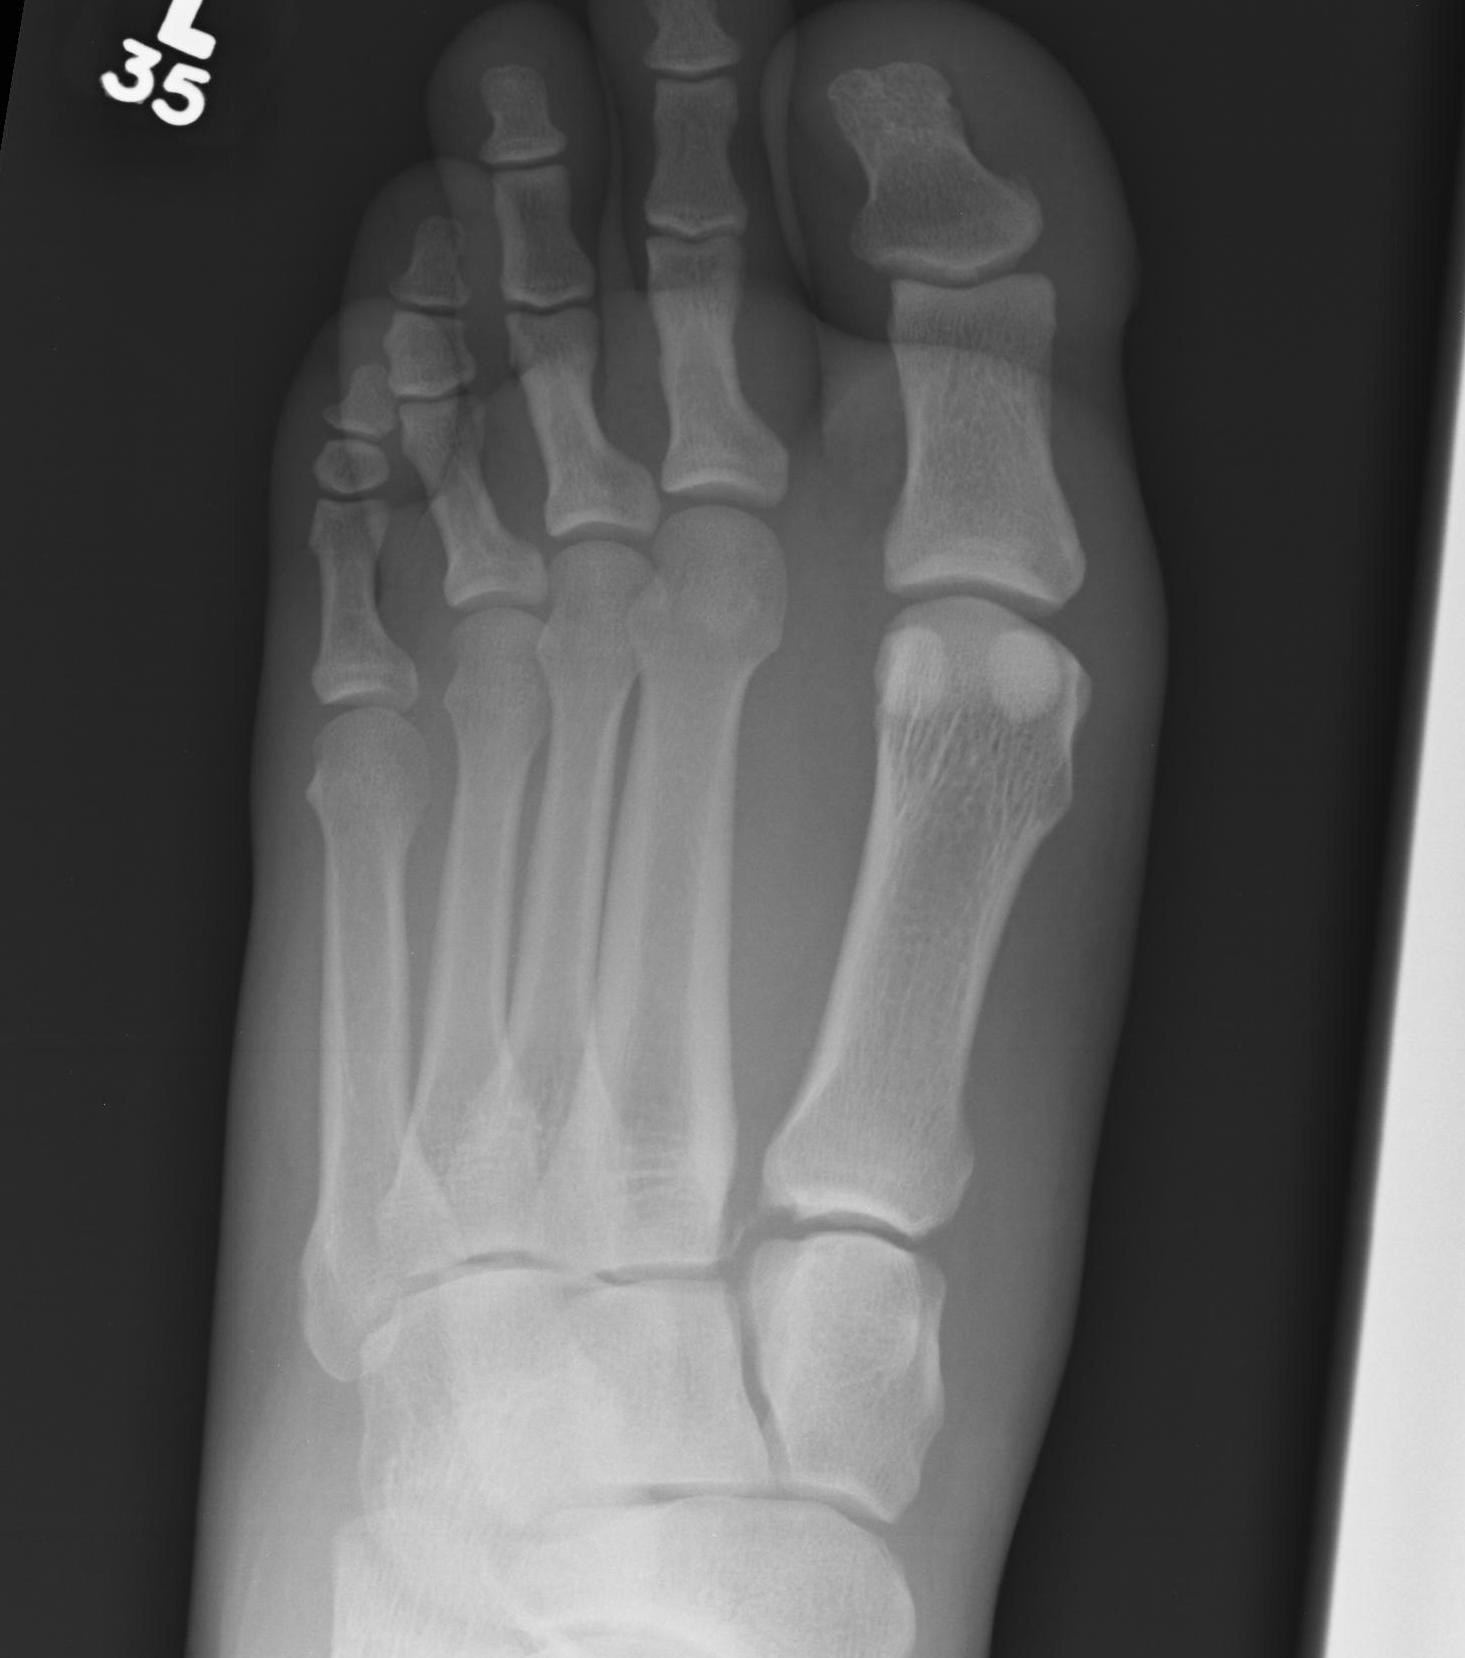

Increased widening of inter-metatarsal distance on weight bearing views

Increased widening of Lisfranc joint with subluxation of the 1st and 2nd metatarsals on weight bearing views

Weight bearing xrays

- weight bearing xrays more sensitive at detecting subtle Lisfranc instability